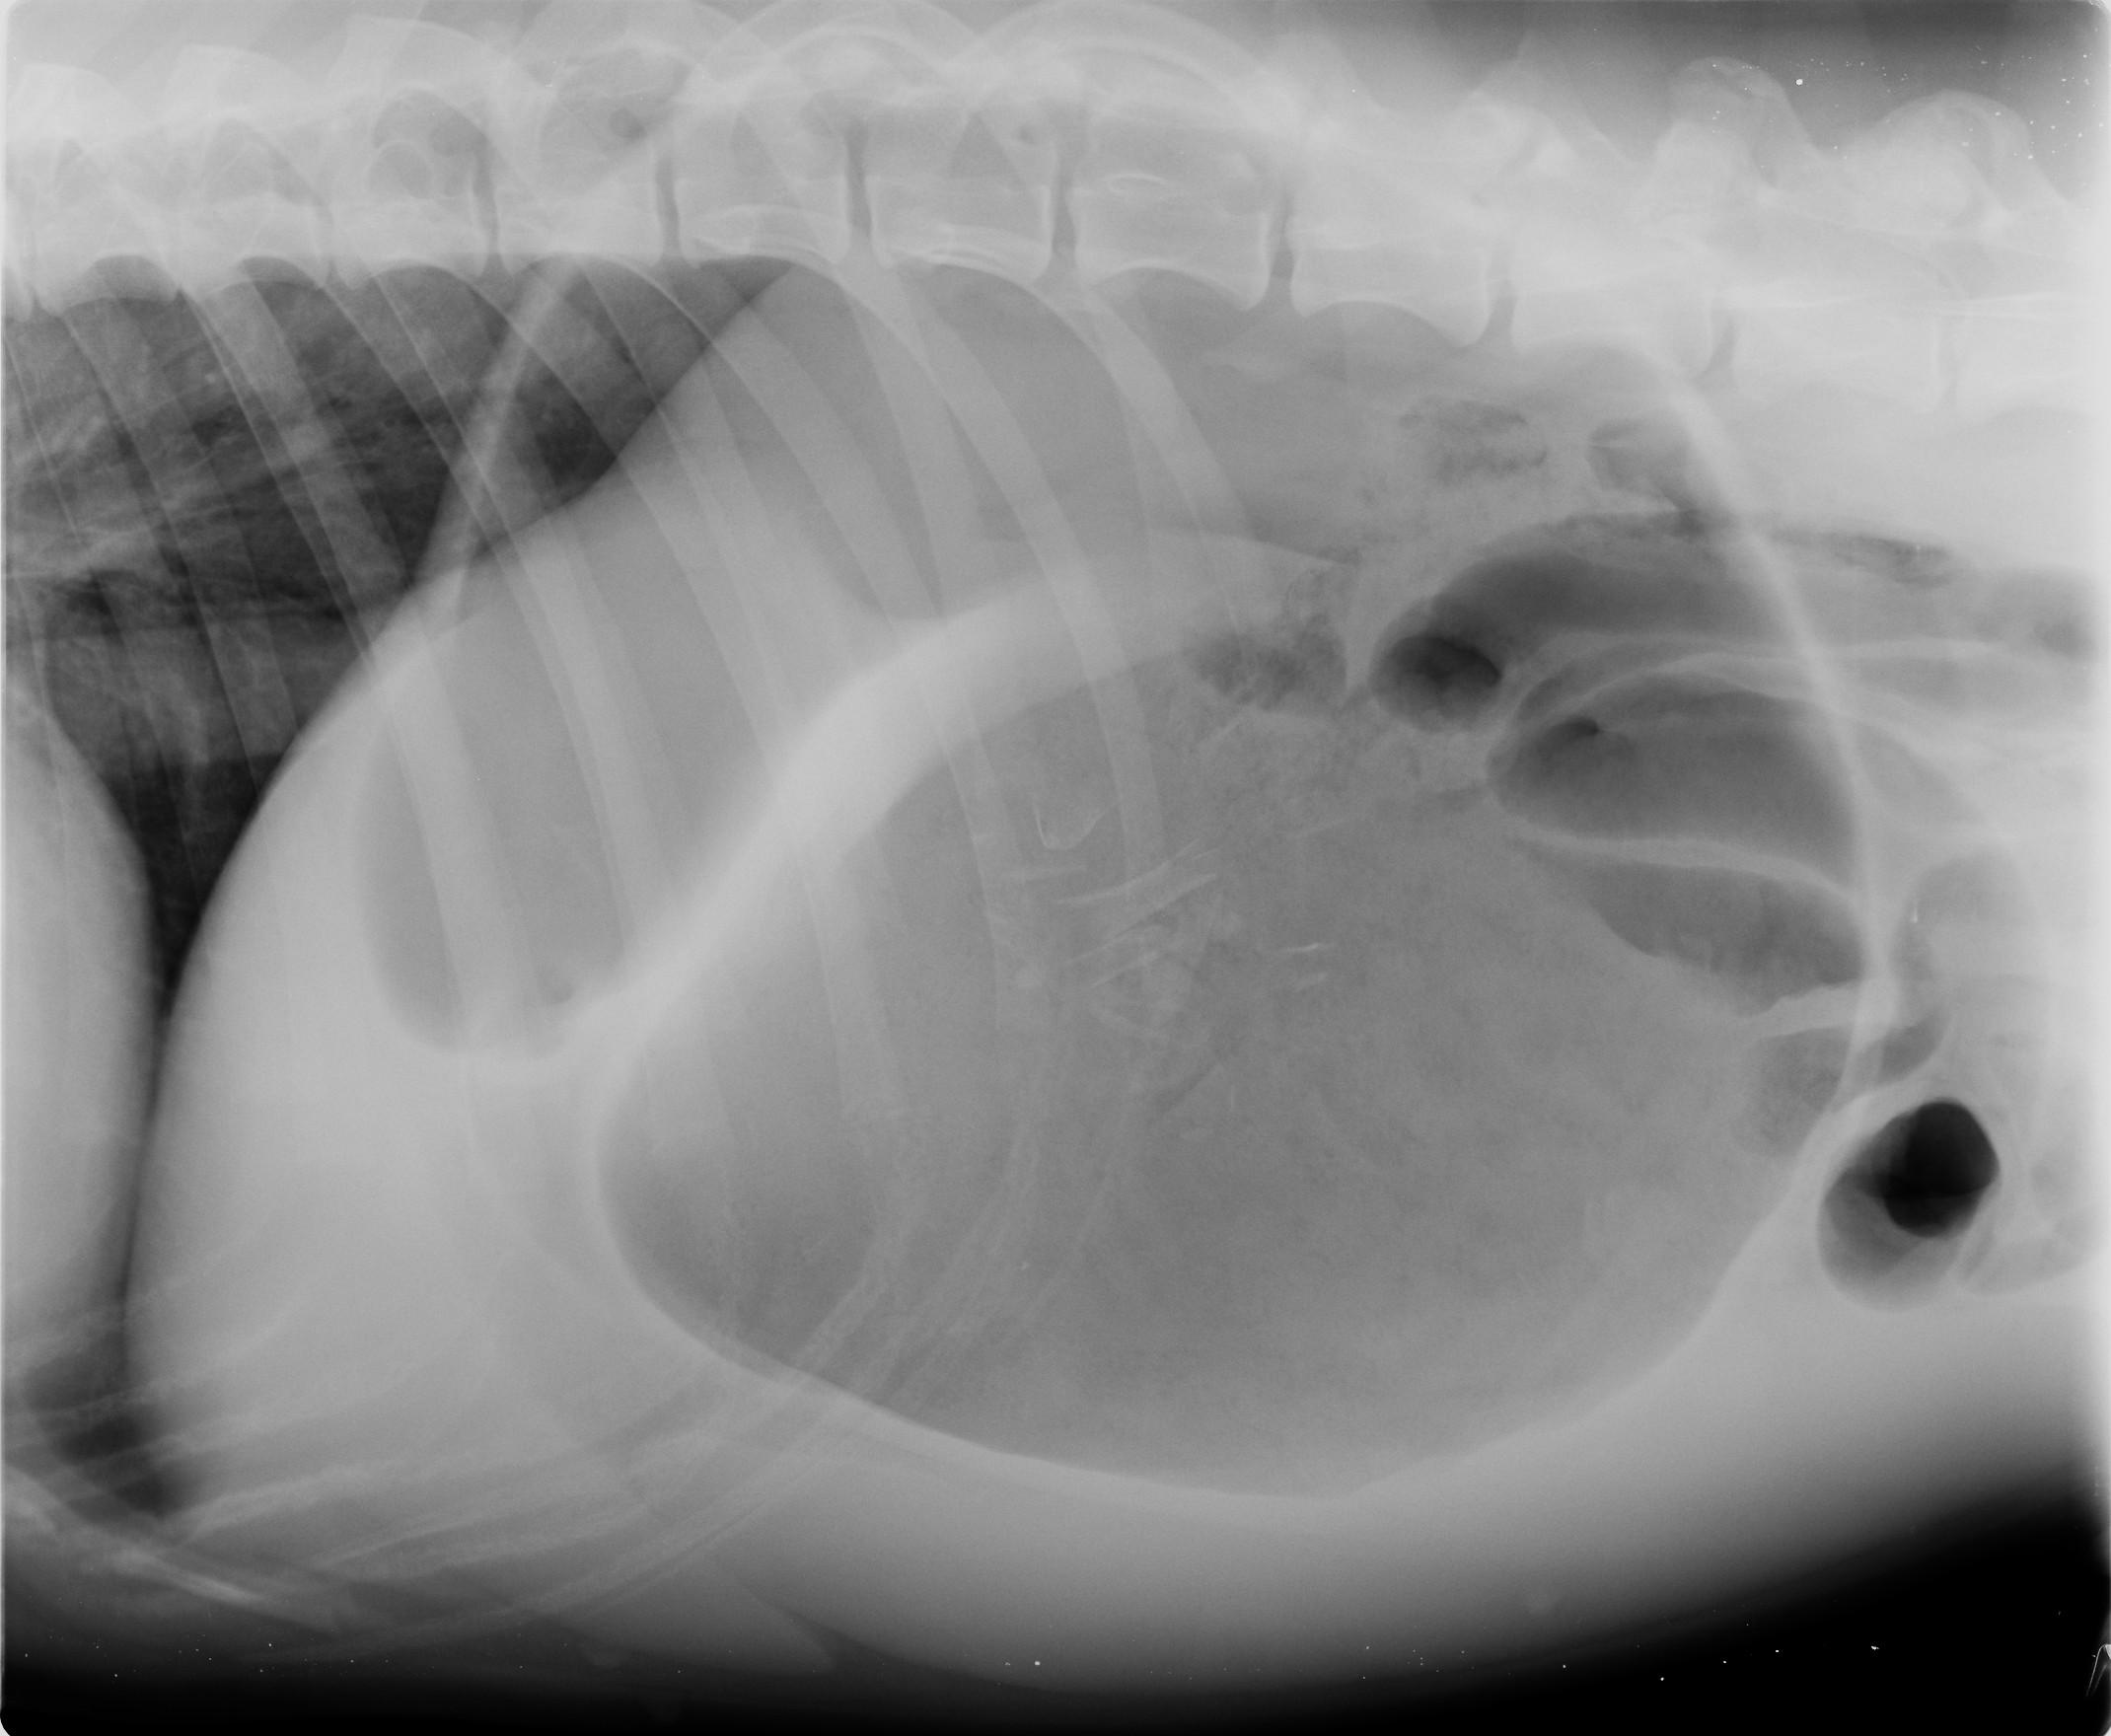

Pour rétablir une oxygénation adéquate des organes, une ou plusieurs perfusions sont mises en place (en fonction de la taille du chien), l’estomac est décomprimé par trocardisation si nécessaire (on place une aiguille dans le haut de l’estomac pour laisser sortir l’air emprisonné et décomprimer l’abdomen). Ensuite une radiographie est réalisée pour permettre de différencier une « simple dilatation » d’une réelle torsion. En cas de dilatation sans torsion, l’animal est tranquillisé et une sonde est placée dans son estomac par la gueule et l’osophage. S’il y a torsion, une chirurgie est nécessaire, en URGENCE, pour détordre l’estomac. A cette occasion, on suturera la paroi de l’estomac à la paroi costale, afin d’éviter toute nouvelle torsion (gastropexie).